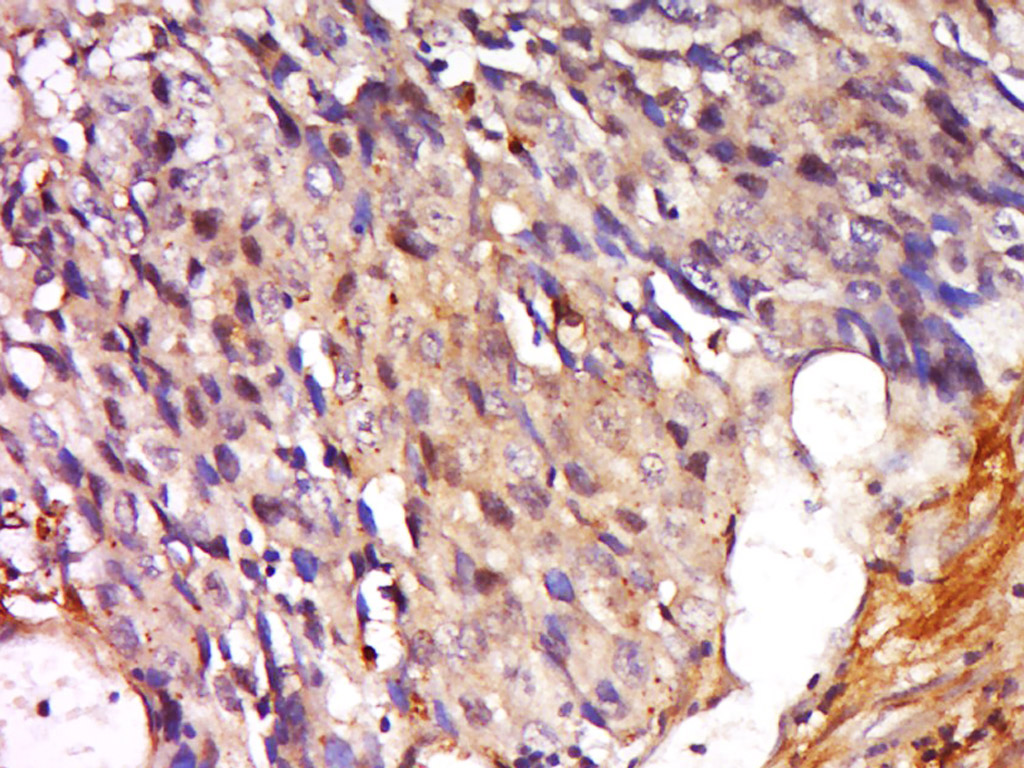

Tissue/cell: human colon cancer; 4% Paraformaldehyde-fixed and paraffin-embedded; Antigen retrieval: citrate buffer ( 0.01M, pH 6.0 ), Boiling bathing for 15min; Block endogenous peroxidase by 3% Hydrogen peroxide for 30min; Blocking buffer (normal goat serum,C-0005) at 37℃ for 20 min; Incubation: Anti-SFRS9 Polyclonal Antibody, Unconjugated(bs-20144R) 1:400, overnight at 4°C, followed by conjugation to the secondary antibody(SP-0023) and DAB(C-0010) staining